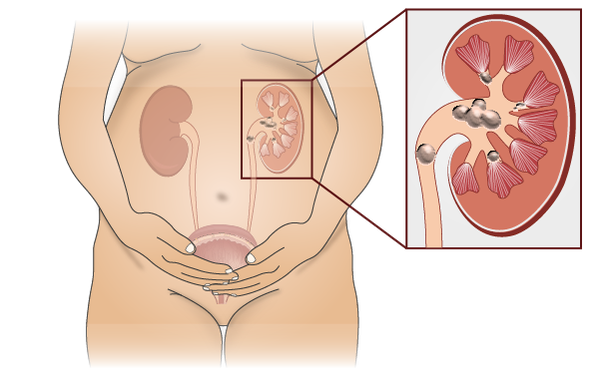

The process of forming stones in the kidney, bladder, and/or urethra (urinary tract) is called urolithiasis. Kidney stones are a common cause of blood in the urine and pain in the abdomen, flank, or groin.

The process of forming a kidney stone, a stone in the kidney (or lower down in the urinary tract). Kidney stones are a common cause of blood in the urine and pain in the abdomen, flank, or groin.

Formation of stone in the kidney is called nephrolithiasis.